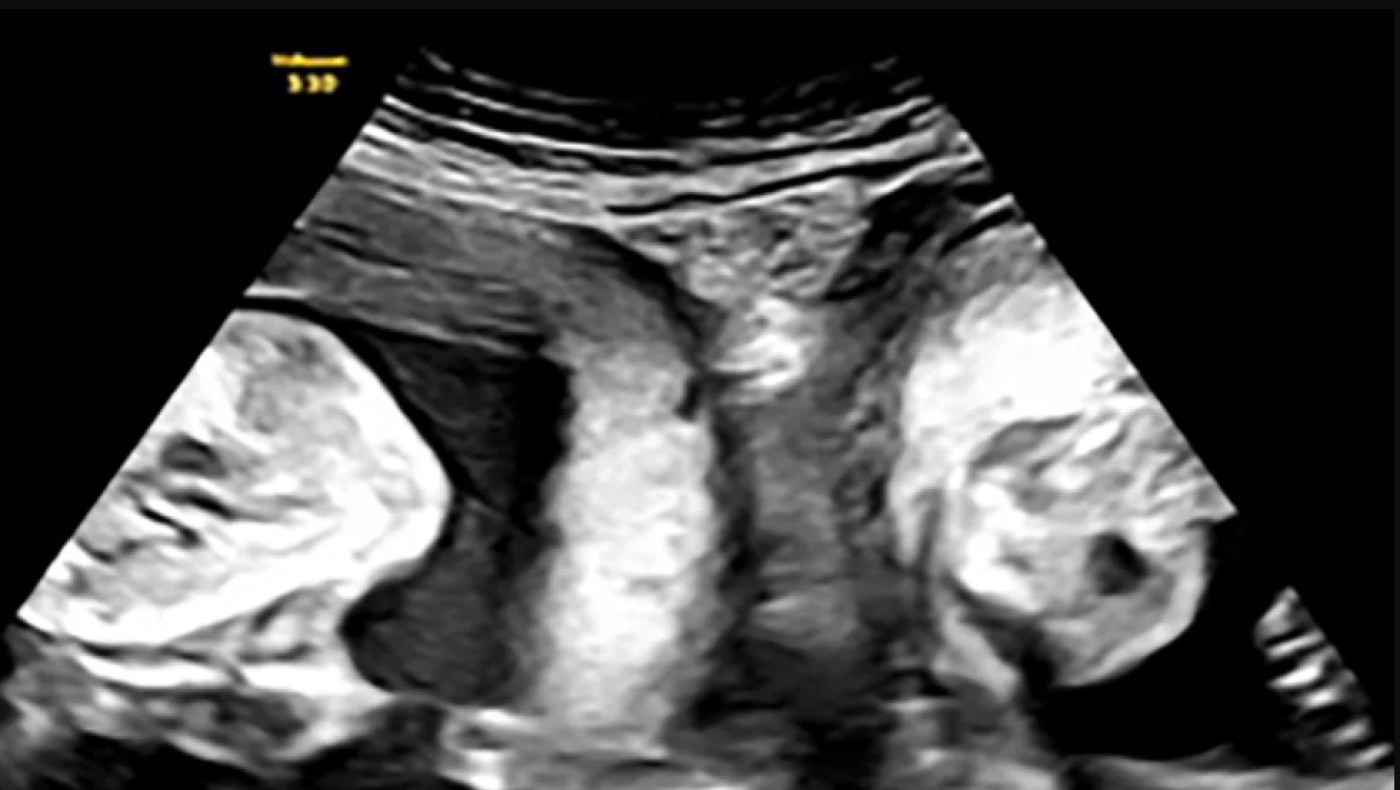

Τον Ιανουάριο, όμως, η Li έμεινε ξανά έγκυος και ανακάλυψε κατά τη διάρκεια ενός υπερηχογραφήματος ότι κυοφορούσε δίδυμα - ένα σε κάθε μήτρα και οι γιατροί του νοσοκομείου «έπεσαν» πάνω στο περιστατικό για να εξασφαλίσουν την επιτυχία της εγκυμοσύνης.

Μετά από στενή ιατρική παρακολούθηση, η γυναίκα κατάφερε να γεννήσει ένα αγόρι βάρους 3,3 κιλών και ένα κορίτσι βάρους 2,4 κιλών, σύμφωνα με το νοσοκομείο.